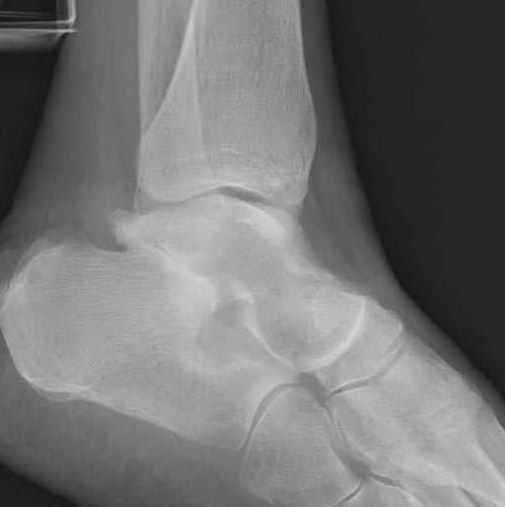

Уважаемые участники русского Ортофорума, поздравляю всех со всеми прошедшими праздниками: Новым годом, Рождеством, Hanukkah, Kwanzaa, желаю участникам всего наилучшего и здоровья.Повреждение таранной кости.Больной 81г автоавария, повреждение таранной кости, здесь снимки.

Какие рекомендации?Djoldas Kuldjanov, MDDepartment of Orthopedic SurgerySt. Louis University Medical Center

Вообще то мало данных: торчит ли осколок под кожей, сопутствующая паталогия (атеросклероз, диабет), сколько времени прошло после травмы? Я думаю, что в данном случае можно ограничиться или небольшим вмешательством вплоть до удаления дистального отломка из небольшого разреза, или наложением аппарата с дистракцией переднего отдела стопы в эквинусе, может быть удастся этот отломок и вправить. Опорная функция в любом случае должна сохраниться при любом варианте лечения, не думаю что будет страдать кровоснабжение таранной кости. Я когда то удалил дистальную половину таранной кости, с последующим анкилозированием в тарано-ладьевидном суставе, хотя более опытные товарищи советовали провести астрагалэктомию, но тем не менее тогда результат оказался хороший. Конечно объязательно назначение препаратов улучшающих микроциркуляцию, противоотечная терапия и т.п. Удачи.